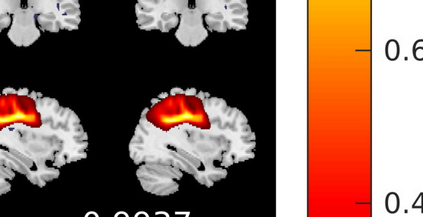

In the last two decades, unsupervised latent variable models---blind source separation (BSS) especially---have enjoyed a strong reputation for the interpretable features they produce. Seldom do these models combine the rich diversity of information available in multiple datasets. Multidatasets, on the other hand, yield joint solutions otherwise unavailable in isolation, with a potential for pivotal insights into complex systems. To take advantage of the complex multidimensional subspace structures that capture underlying modes of shared and unique variability across and within datasets, we present a direct, principled approach to multidataset combination. We design a new method called multidataset independent subspace analysis (MISA) that leverages joint information from multiple heterogeneous datasets in a flexible and synergistic fashion. Methodological innovations exploiting the Kotz distribution for subspace modeling in conjunction with a novel combinatorial optimization for evasion of local minima enable MISA to produce a robust generalization of independent component analysis (ICA), independent vector analysis (IVA), and independent subspace analysis (ISA) in a single unified model. We highlight the utility of MISA for multimodal information fusion, including sample-poor regimes and low signal-to-noise ratio scenarios, promoting novel applications in both unimodal and multimodal brain imaging data.